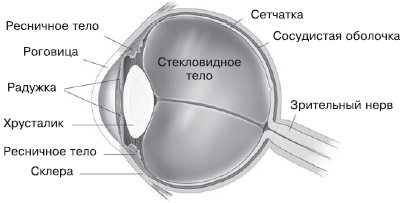

КТ-графики и изображение строения глаза